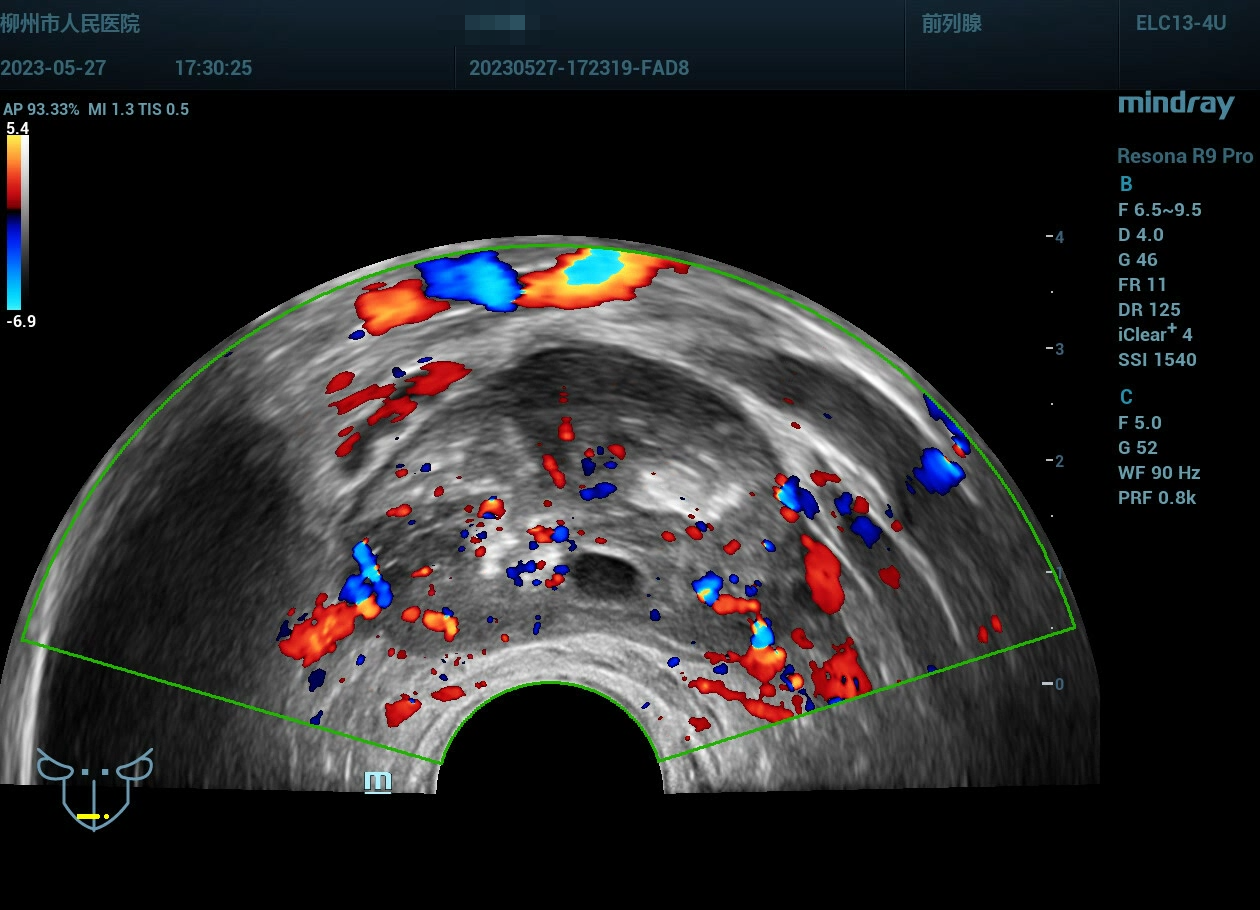

病史为年轻的男性,主要症状为尿痛、血精。

精囊腺的超声图像表现:肿胀、回声紊乱。